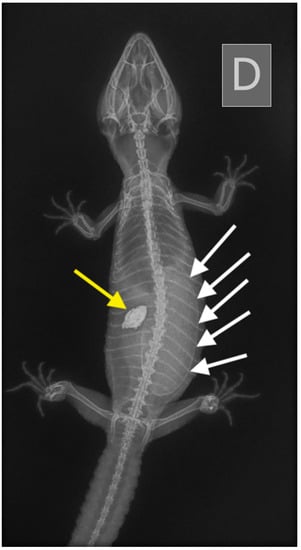

2.2.2. Case 2